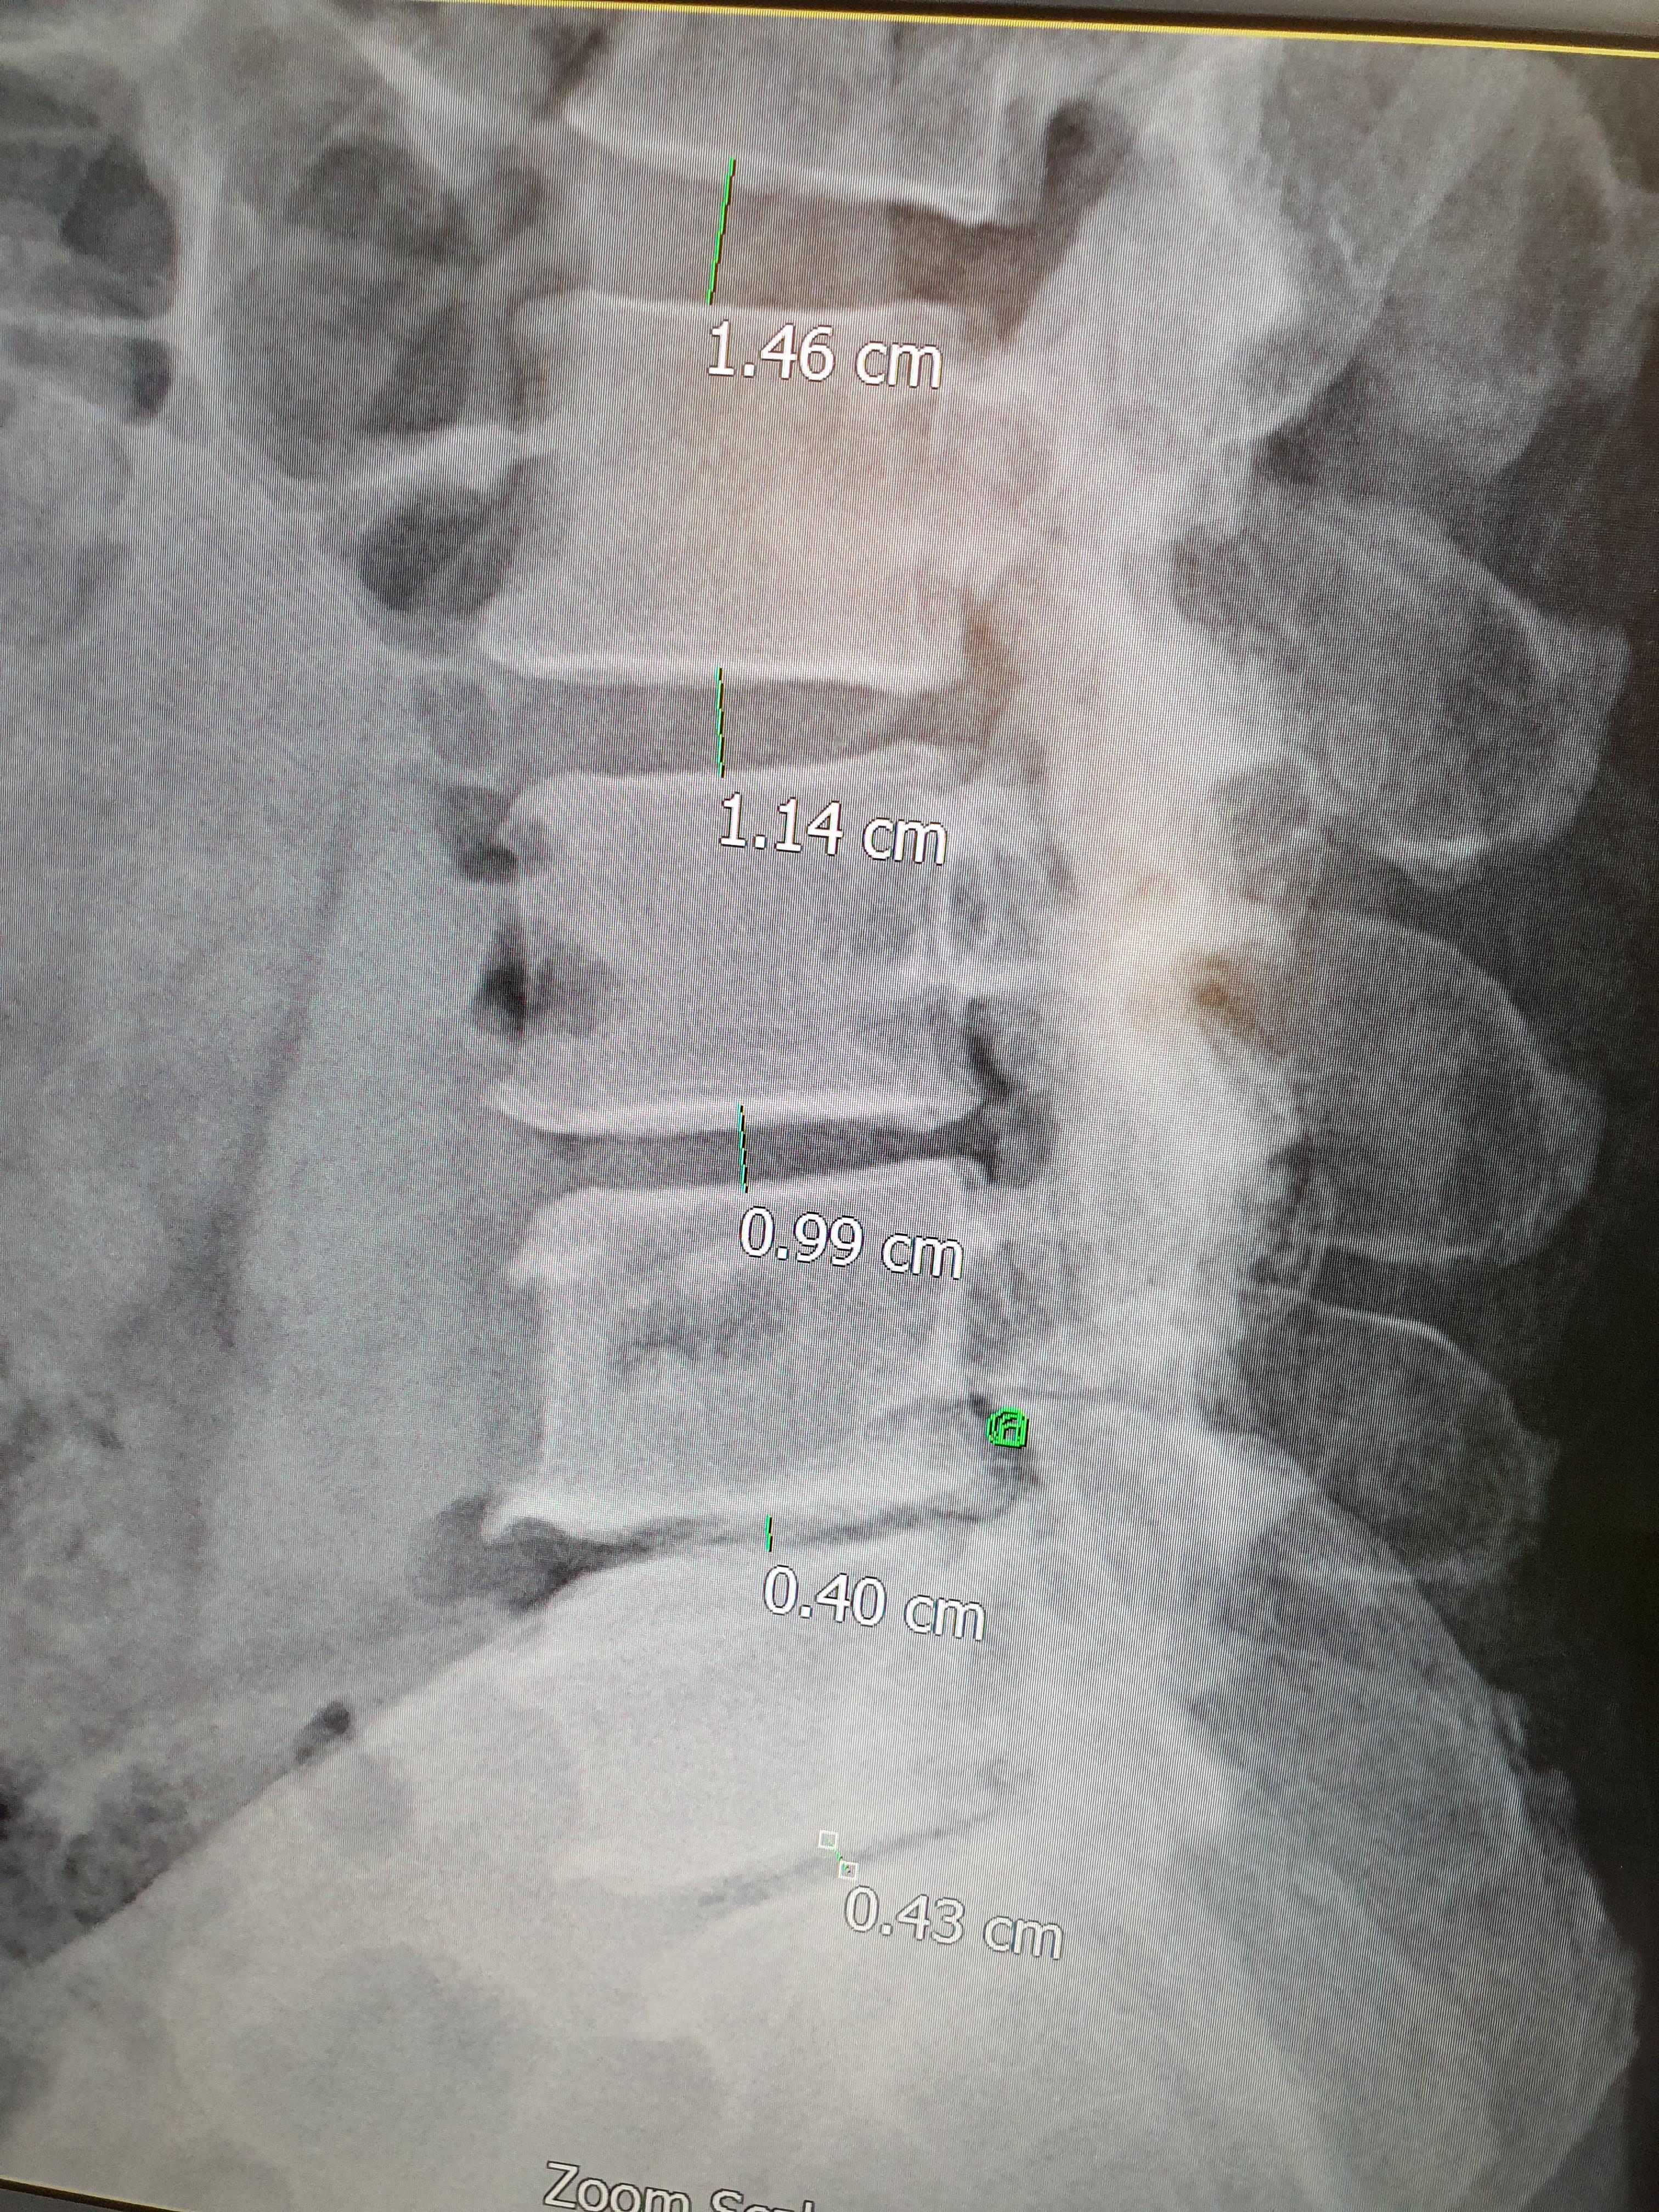

의사는 X-ray 사진을 보더니 제게 "디스크 간격이 없다"고 말했습니다. 또한, 허리근육이 많이 약화되어 있다고 했습니다. 허리는 뼈가 아니라 근육과 코어가 지탱하는 구조물이라는 사실을 그제야 실감했습니다. 활동량이 줄어들면 가장 먼저 약해지는 부위가 복부, 척추기립근, 둔근이라고 합니다. 제 경우도 정확히 그랬습니다.

근육이 약해지면 디스크에 직접 압력이 실립니다. 제 경우는 디스크 협착증 말기 단계였습니다. 신경이 지나가는 통로가 좁아지면서 통증과 저림이 나타나는 질환입니다. 솔직히 "협착증"이라는 단어를 들었을 때는 그런가했지만, X-ray 사진에 나타난 좁아진 디스크상태를 보니 많이 당황스러웠습니다.